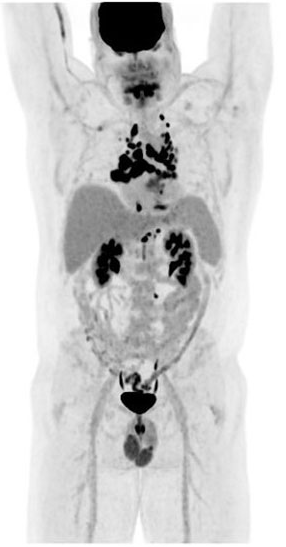

Are there other organs in our body that will uptake the tracer F-18 FDG?

Brain

Kidneys

Bladder

Variable of the heart

What are 5 limitations that may appear on a PET scan aside from the intended cancer?

Infections – COVID-19

Inflammation

Atelectasis

Healing tissue – post-surgery

Muscle activity

If the patient doesn’t empty their bladder before we scan the PET images, their bladder will be visibly ‘hot’ and interfere with the images